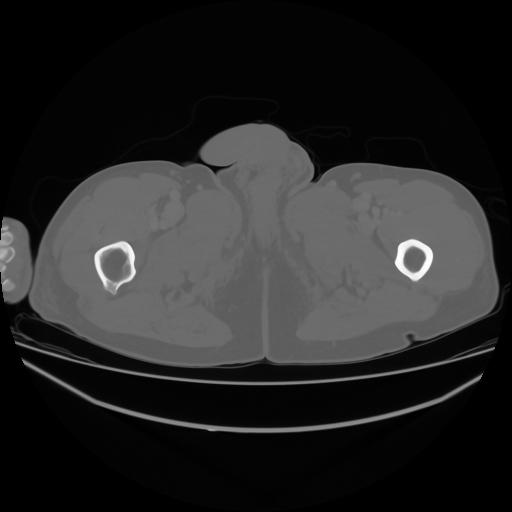

4 CUERPO,CE,Axial,3.0,CUERPO,,